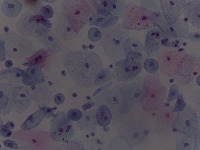

Medical Diagnostics: This model can be used in the healthcare industry to provide high-speed automated analysis of pathology slides, determining whether cells are normal or abnormal, and assisting in diagnosis of various diseases such as cancer.

Scientific Research: Researchers studying cell biology or genetics can use this AI model for their studies on cellular abnormalities and diseases. This can accelerate the onset of breakthroughs in medical science.

Pharmaceutical Applications: Pharmaceutical companies can use this model in drug discovery and development process. By identifying how different medications affect normal and abnormal cells, they can speed up and enhance their research.

Educational Tool: This AI model could serve as a rich educational tool in courses related to biology, medicine and health sciences, helping students to visualize and understand differences between normal and abnormal cells.

Personalized Medicine: This model can be used to analyze patients' cells to create personalized treatment plans. Understanding an individual's cellular structure could help healthcare professionals tailor treatments to the patient's specific needs.